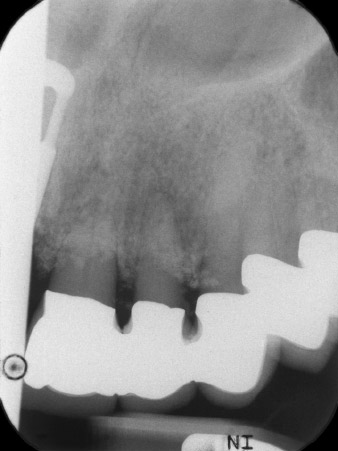

radiologischer Ausgangsbefund

Abb. 1: Der radiologische Ausgangsbefund zeigt eine erneuerungsbedürftige verblockte Kronenversorgung. Beim Abnehmen werden die Zähne 21 und 22 unbeabsichtigt extrahiert.

Bei der Erstvorstellung sind die Zähne 21, 22 und 23 mit 19 Jahre alten verblockten Kronen versorgt. Sie sind über ein Geschiebe mit Implantaten an den Positionen 12/11 verbunden (vgl. Abb. 2). Das Röntgenbild zeigt einen horizontalen Knochenverlust um die Zähne 21 und 22 (Abb. 1).